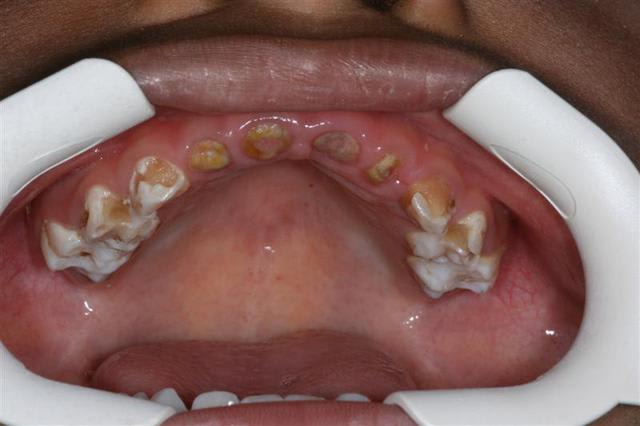

ce cas est ds mon cab,patient pas aisé qui se fait soigner ailleurs mais fait un effort financier pr ses enfants

pas de photos sur les cas à l'hosto le jeudi matin(pas le temps et pas facile) mais TOUS les gamins sans exception entre 2 et 14 ans ont ce mme profil carieux)

Ploc, sur le cas que tu montres, tu as fais les pulpecs sur les incisives et juste fermé comme ça ? Le gamin a une pap en plus ?

pr choip

non j'ai juste traité et gardé les racines pr garder l'espace

c'est

- un compromis de temps(il avait 4ans1/2)

-un compromis financier:ce n'était pas si important pr l'avenir de faire une PAP alors pourquoi la faire à part remplir le mien de portefeuille,d'autant que cela veut dire envoyer l'empreinte en metropole avec les couts de chronopost qui viennent encore augmenter le devis